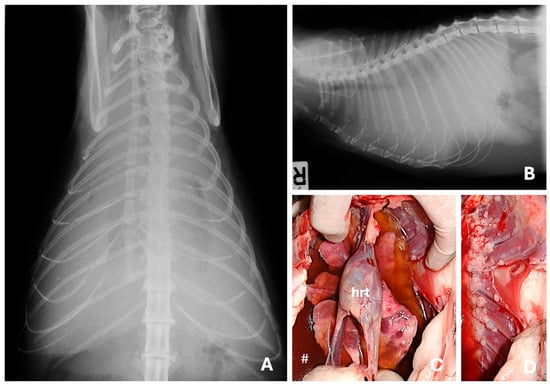

4.1. Radiography

- Otoni, C.C.; Rahal, S.C.; Vulcano, L.C.; Ribeiro, S.M.; Hette, K.; Giordano, T.; Doiche, D.P.; Amorim, R.L. Survey Radiography and Computerized Tomography Imaging of the Thorax in Female Dogs with Mammary Tumors. Acta Vet. Scand. 2010, 52, 20. [Google Scholar] [CrossRef]

- Lekshmi, S.L.; Nair, S.S.; Sajitha, I.S.; Ramankutty, S.; Narayanan, M.K.; John Martin, K.D. Radiographic Assessment of Pulmonary Metastatic Lesions in Superficial Cutaneous and Mammary Neoplasms in Dogs. J. Vet. Anim. Sci. 2021, 52, 393–398. [Google Scholar] [CrossRef]

- Forrest, L.J.; Graybush, C.A. Radiographic Patterns of Pulmonary Metastasis in 25 Cats. Vet. Radiol. Ultrasound 1998, 39, 4–8. [Google Scholar] [CrossRef]